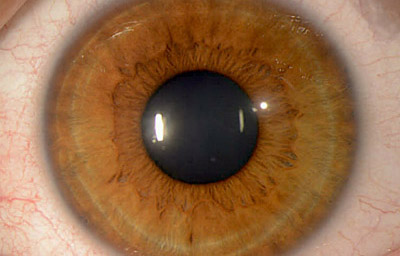

Foto de un Iris humano adulto, con residuos avasculares pigmentados de la membrana pupilar, viniendo del circulo menor. No tiene criptas.

Tomada del archivo fotografico del Dr. CB